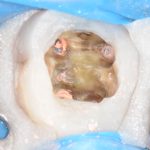

La perforazione del pavimento della camera pulpare dei pluriradicolati è una delle principali complicanze che possono presentarsi durante i trattamenti endodontici con prognosi spesso sfavorevole. In questo caso clinico si è optato per una terapia conservativa, che ha permesso di salvare l’elemento, utilizzando tecniche la cui efficacia è dimostrata da molti studi in letteratura.